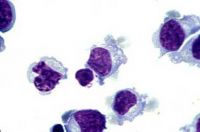

Makrofág

Makrofág.